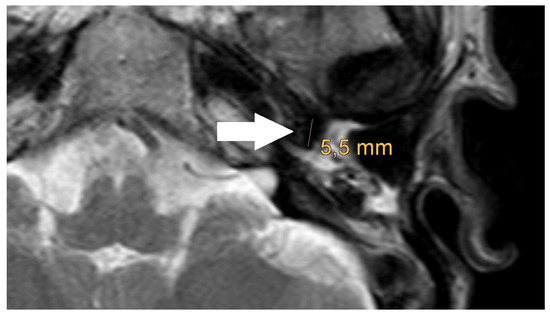

| PORP | 2.0 mm | 3.1 mm | 5.4 mm |

| TORP | 3.6 mm | 4.7 mm | 7.2 mm |

| Mesh | 0.1 mm | 3.6 mm | 5.8 mm |